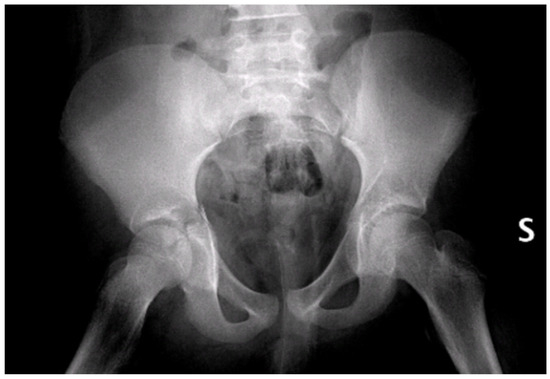

Figure 2.

Pelvic X-rays at admission time. S = left side.

Initial radiographs (Figure 2) and CT imaging revealed an open fracture of the right tibia with involvement of the tibial plateau (Schatzker IV) and a vertical fracture line extending below the tibial tuberosity; a transverse fracture of the right acetabulum with disarticulation of the triradiate cartilage (Figure 3); a suspected fracture at the level of the left lesser trochanter; bilateral pulmonary contusions (segments of the upper and lower lobes); a thin parafalcine and paratentorial intracranial haemorrhage without mass effect; no craniofacial or cervical spine fractures; no solid-organ injury in the abdomen; a small simple cyst in the left kidney; and developmental changes in thoracic vertebral bodies (D6–D8) without acute traumatic lesions. The patient was haemodynamically stable after initial resuscitation. Neurovascular examination of the lower limbs was normal at presentation.